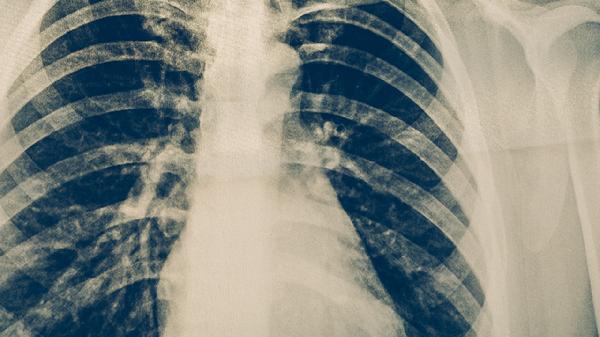

肺结核早期可遵医嘱使用异烟肼片、利福平胶囊、吡嗪酰胺片、乙胺丁醇片、链霉素注射液等抗结核药物。肺结核是由结核分枝杆菌感染引起的慢性传染病,需规范联合用药以降低耐药风险。

肺结核患者除规范用药外,应保证充足营养摄入,多食用高蛋白食物如鸡蛋、鱼肉,适量补充维生素丰富的蔬菜水果。避免辛辣刺激性食物,戒烟戒酒。治疗期间严格遵医嘱完成全程化疗,定期复查胸部影像学和痰菌检查。出现药物不良反应时及时就医调整方案,不可自行增减药量或中断治疗。保持居住环境通风良好,咳嗽喷嚏时注意呼吸道隔离,密切接触者需进行结核筛查。